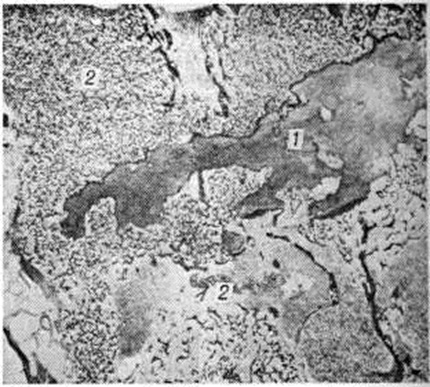

Новообразованная костная ткань лишена функциональный дифференцировки, однотипна при любой локализации процесса. Эта ткань разрастается среди предсуществующих костных структур, постепенно занимая все более значительные пространства кости. Она построена из мелких, примитивных афункциональных костных перекладин, частично сохраняющих остеоидный характер. Рисунок костных пластин неотчётливый. Количество и зрелость костных перекладин могут быть различными. Костные перекладины окружены нежно волокнистой остеогенно-потентной тканью (рисунок 8), содержащей большое количество кровеносных капилляров, вокруг которых располагаются мелкие одноядерные клетки с тёмно-базофильными ядрами и узким розоватым ободком цитоплазмы. Новообразованная костная ткань отличается признаками интенсивного костеобразования и резорбции неполноценного костного вещества — вблизи костных перекладин располагаются цепочки и скопления клеток остеобластического ряда, на поверхности костных перекладин в лакунах залегают многочисленные остеокласты.